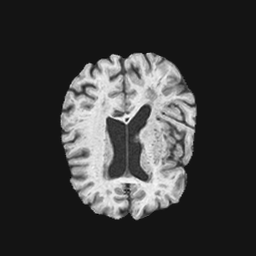

Exp. 1: Segmented adult brain data is used to evaluate our network’s regression performance with known ground truth Tisubscript𝑇𝑖T_{i}. 85 brains from the ADNI data set[1] were randomly selected; 70 brains for ΩtrainsubscriptΩ𝑡𝑟𝑎𝑖𝑛\Omega_{train} and 15 brains for ΩvalidationsubscriptΩ𝑣𝑎𝑙𝑖𝑑𝑎𝑡𝑖𝑜𝑛\Omega_{validation}. Fig. 2 shows an example slice of the ground truth and the reconstructed ΩΩ\Omega.

Refer to caption

(a)

(b)

(c)

(d)

Figure 2: Example slice from the segmented adult brain MRI data set (a); reconstruction from 300 ωisubscript𝜔𝑖\omega_{i} based on SVRNet regression without SVR (b); SVR initialised with SVRNet predictions after eight iterations of SVR (c). Note that SVRNet (b) predicts individual slice transformations only from image intensities without any initial world co-ordinates of the sampled slice. (d) shows the achieved PSNR in dB when comparing the volumes of (b) and (c) to (a).

Reconstructing from Ti^^subscript𝑇𝑖\hat{T_{i}} initialisation without SVR yields a PSNR of 23.7 ±plus-or-minus\pm 1.09; with subsequent SVR the PSNR increases to 29.5±plus-or-minus\pm2.43 when tested on 15 randomly selected test volumes after four iterations of SVR.